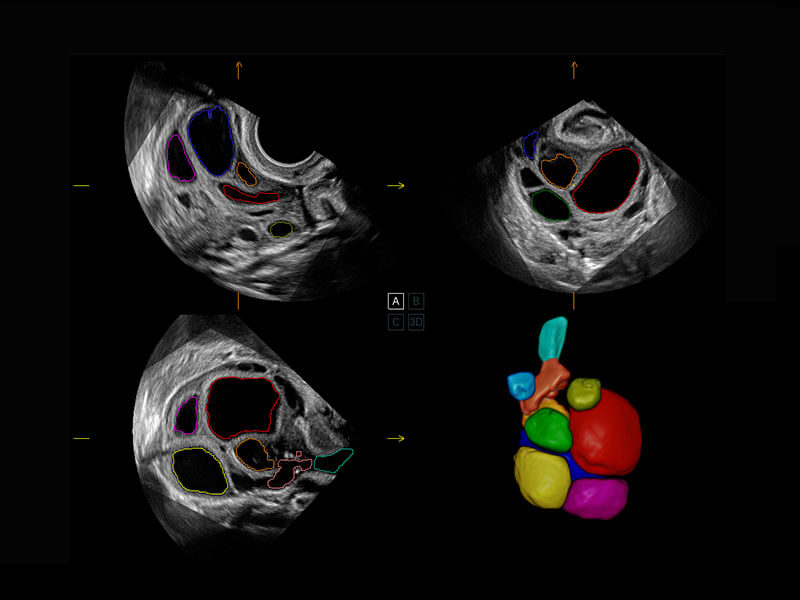

P60搭載一系列胎兒心臟成像技術(shù),實(shí)現(xiàn)精細(xì)的胎兒心臟評(píng)估。

四腔切面

四腔心血流

右室雙出口

胎心容積成像